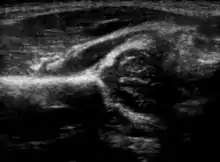

Hip ultrasound

Imaging

Hip dysplasia can be diagnosed by ultrasound[42] and projectional radiography ("X-ray").[43] Ultrasound imaging is generally preferred at up to 4 months due to limited ossification of the femoral head up until then, and is the most accurate method for imaging of the hip during the first few months after birth. However, in most instances, ultrasound screening should not be performed before 3 to 4 weeks of age because of the normal physiologic laxity.[44][notes 1] When universal with targeted ultrasound screening was compared, the former results in an insignificant reduction in the late diagnosis of hip dysplasia, which is why universal ultrasonographic screening of newborn infants is not recommended by the American Academy of Pediatrics.[11]